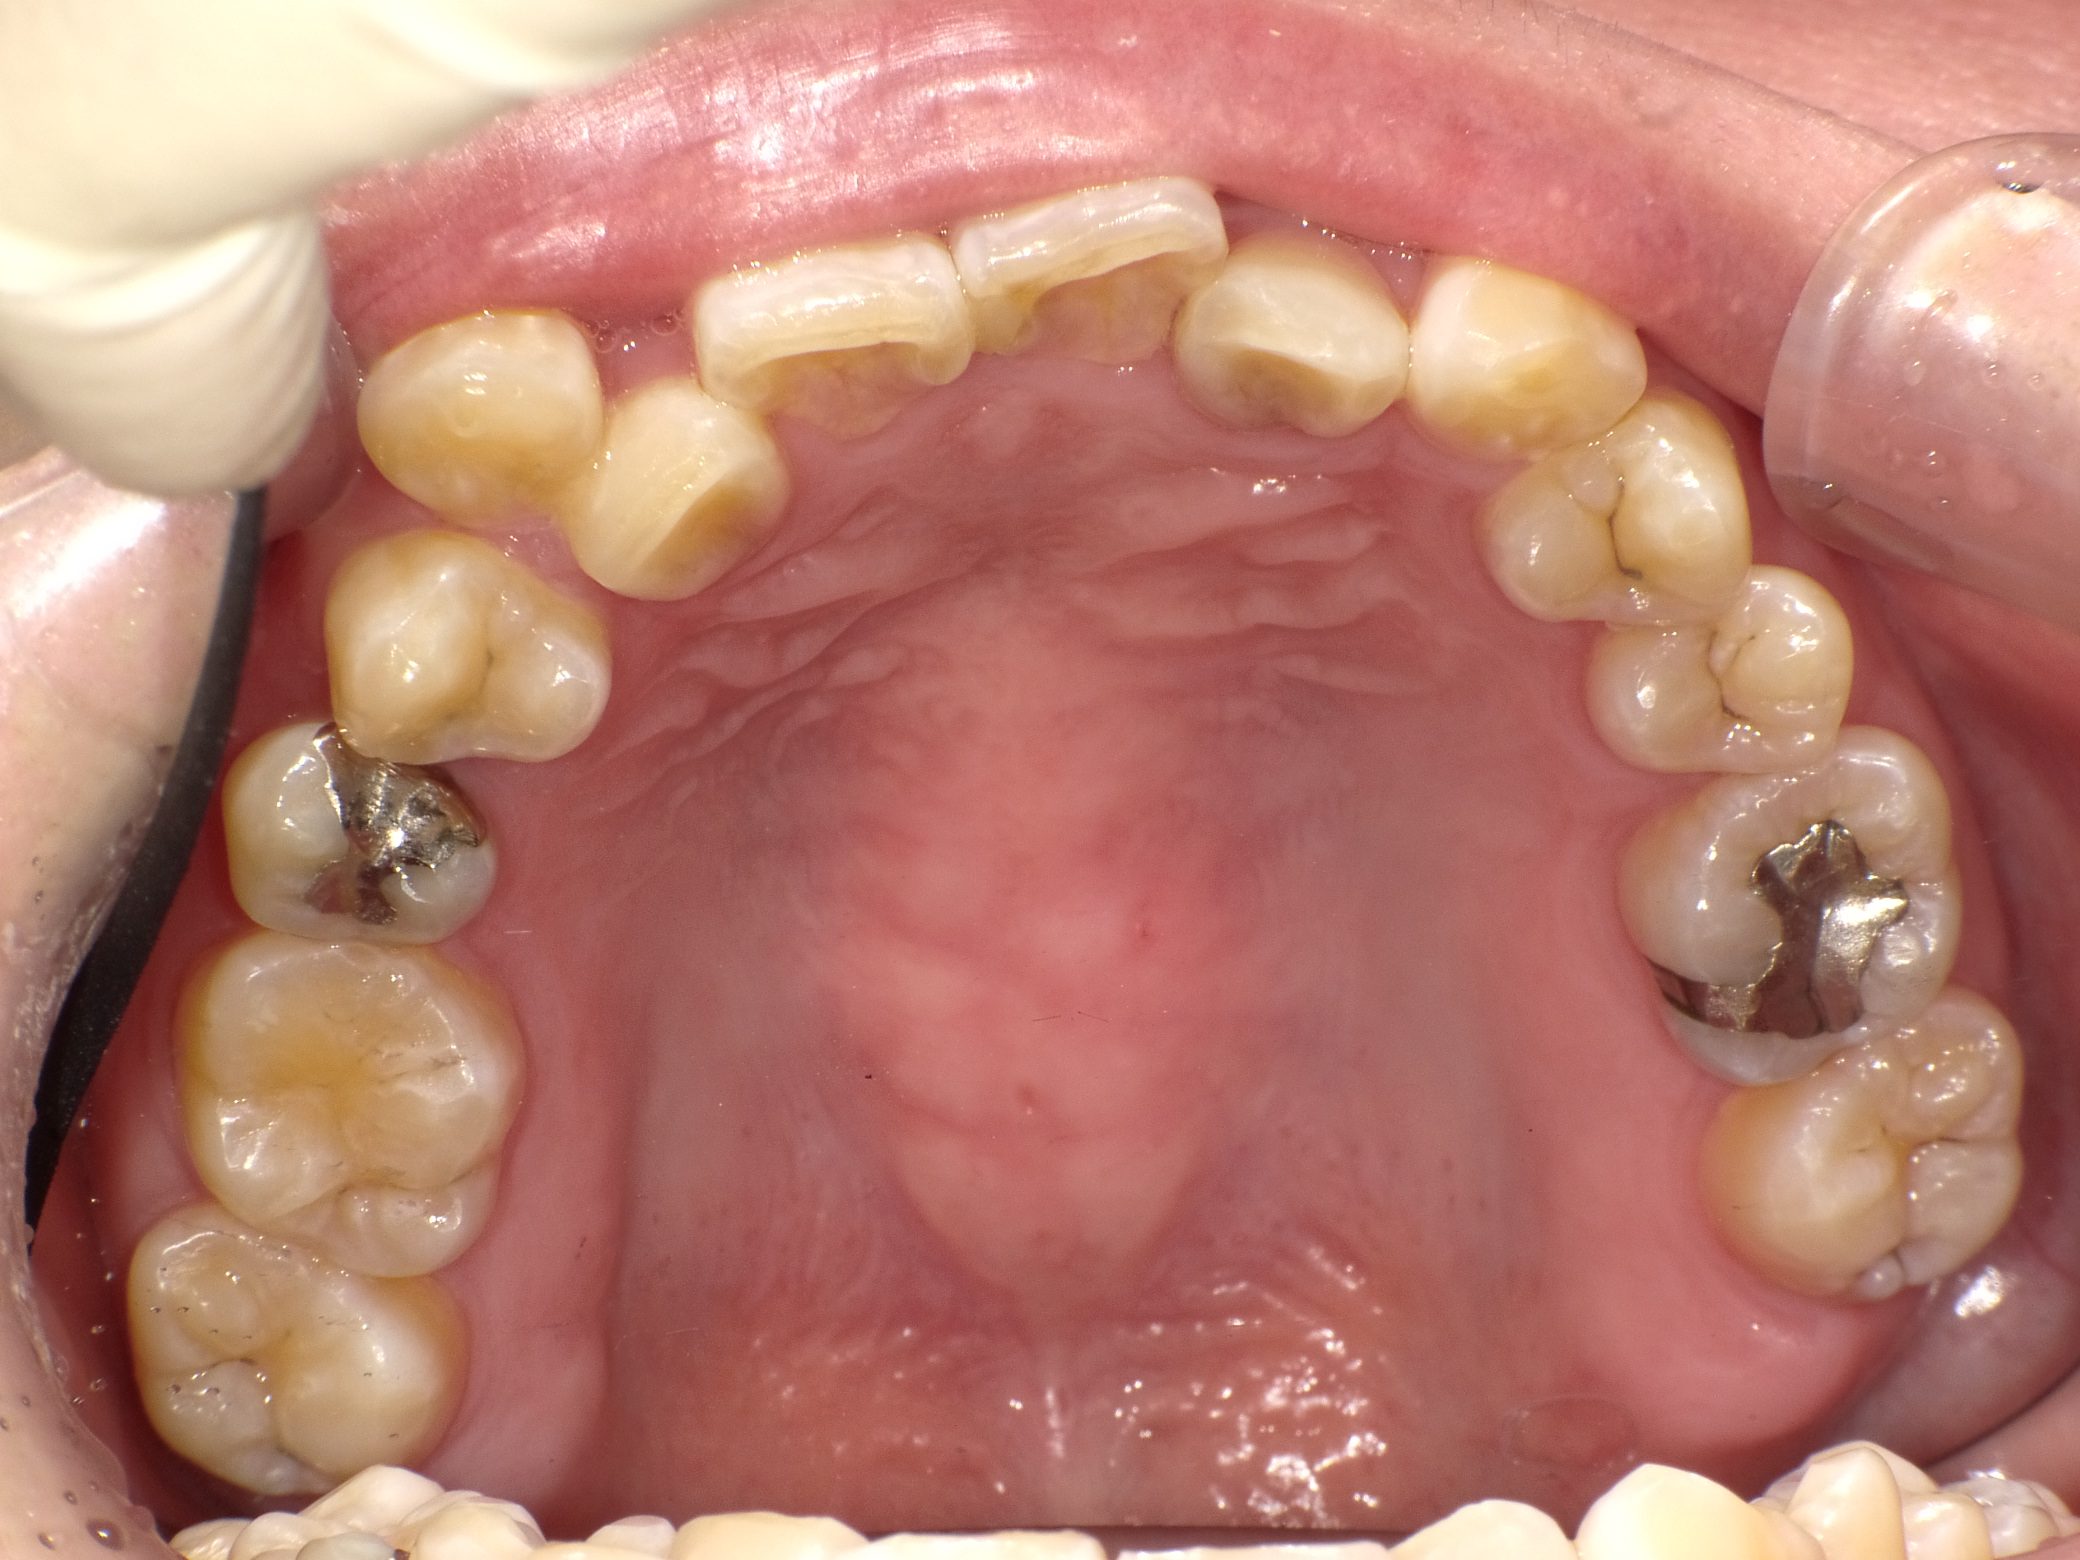

Before

After

【社会人】インビザラインフル 反対咬合(受け口)を改善 下顎前歯1本抜歯

全く装置の浮きがなくしっかり使ってくれたので2年で終了しました。

10年前の治療ですが、今もしっかり後戻りせずに歯並びを保たれています。